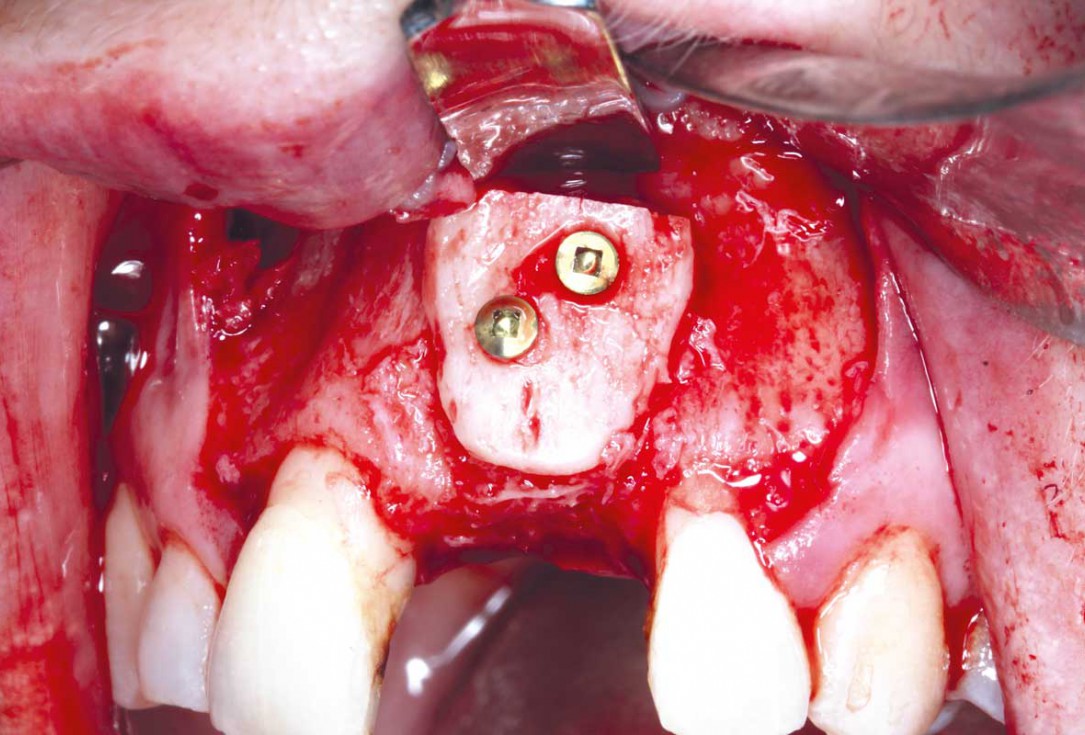

9/35 - Stabilisation of the bone block with two 10 mm fixation screws placed oblique. Sharp edges of the block were polished to avoid defeasance in the soft tissue healingBlock grafting in the aesthetic zone with maxgraft®, Jason® membrane and cerabone® - Dres. H. Maghaireh and V. Ivancheva

10/35 - Stabilisation of the bone block with two 10 mm fixation screws placed oblique. Sharp edges of the block were polished to avoid defeasance in the soft tissue healingBlock grafting in the aesthetic zone with maxgraft®, Jason® membrane and cerabone® - Dres. H. Maghaireh and V. Ivancheva